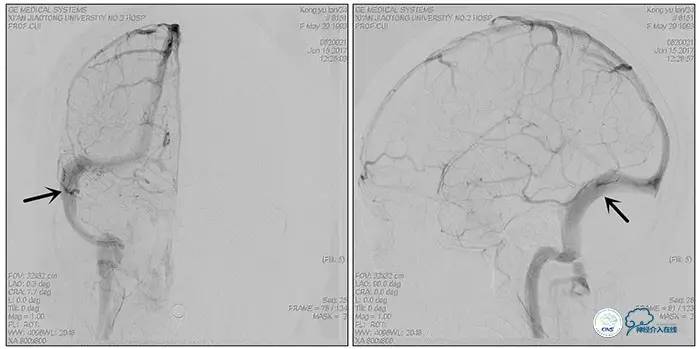

术中造影

术后造影

狭窄较前有改善

术中右侧ICA造影

右侧ICA斜位及窦内造影

右侧ICA斜位

窦内造影及路图